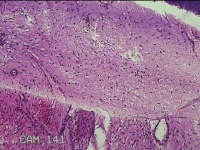

宫颈组织

性别

女

年龄

31岁

临床诊断

宫颈上皮内瘤变

一般病史

发现宫颈CIN2 2个月。

标本名称

大体所见

灰白暗红色组织2.8x1.8x0.3cm一块,表面糜烂,切面灰白暗红色,质软。

所提供图片不具有诊断价值。